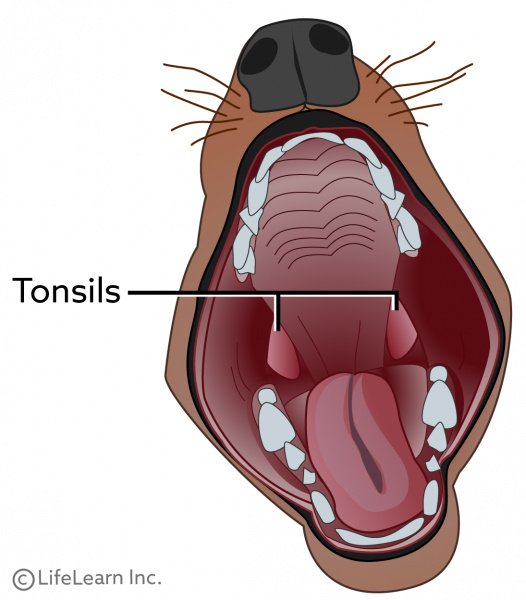

◆ 편도선염과 부종

양쪽 편도선이 부어있는 것 같았어요 특히 왼쪽 편도선은 출혈까지 확인되었는데

편도선염에 대해서 알아볼까요?출처 https://vcahospitals.com/

- 편도선은 어디에 있으며 무엇을 합니까?편도선은 림프절과 비슷한 역할을 하는데 주로 감염에 대해 면역을 지켜주는 역할을 합니다. 편도선은 한 쌍으로 인후부 뒷면에 위치하고 있어서 염증이 생기면 튀어나와 버립니다.